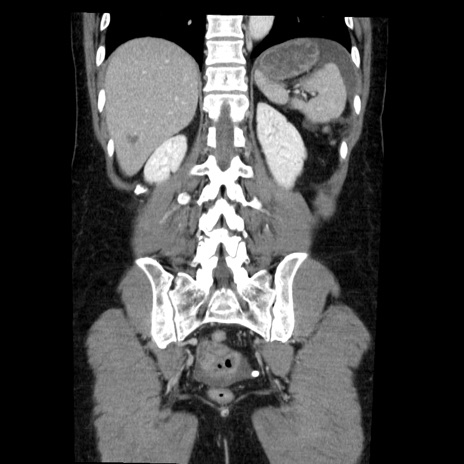

症例6(冠状断像)

【症例】50歳代女性

【主訴】下腹部痛

【既往歴】卵巣癌術後(8年前に当院で卵巣摘出)